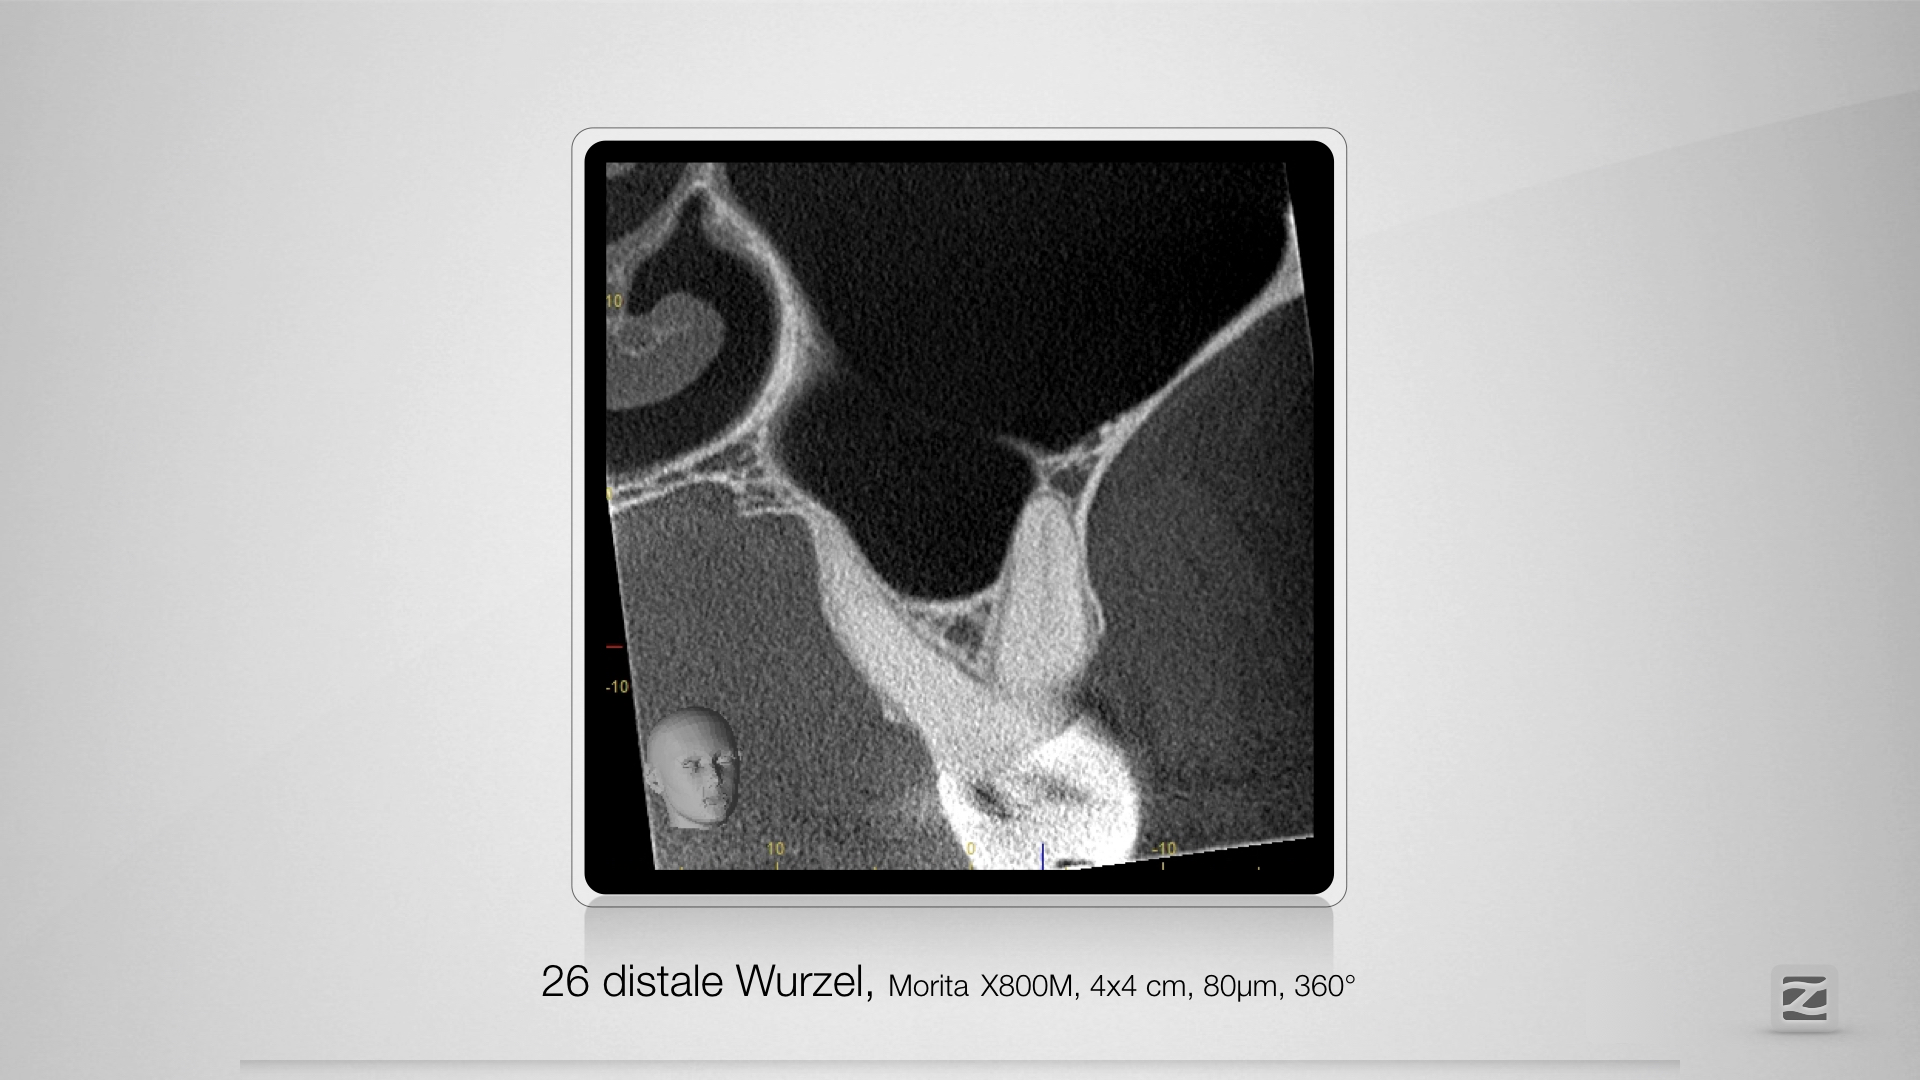

26D.009

Ausschlussdiagnostik